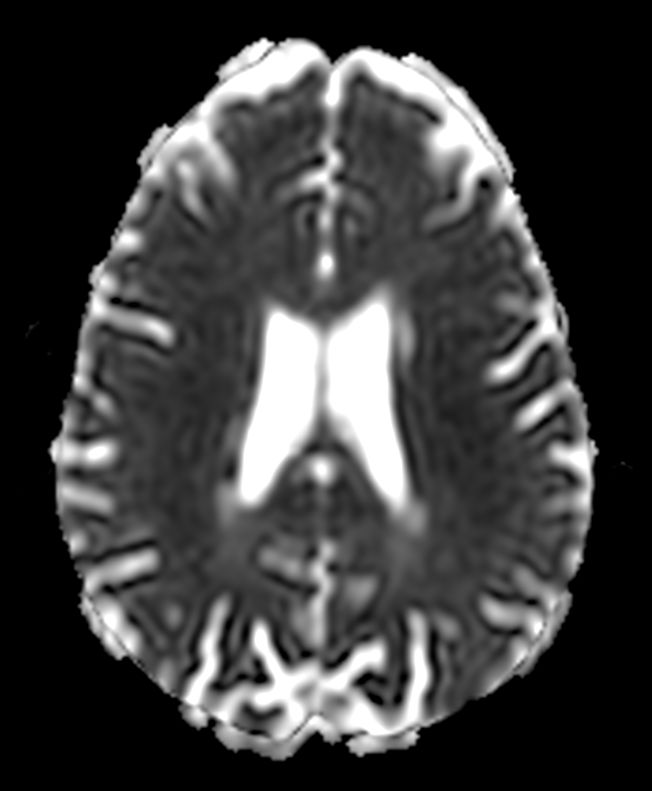

DWI b1000